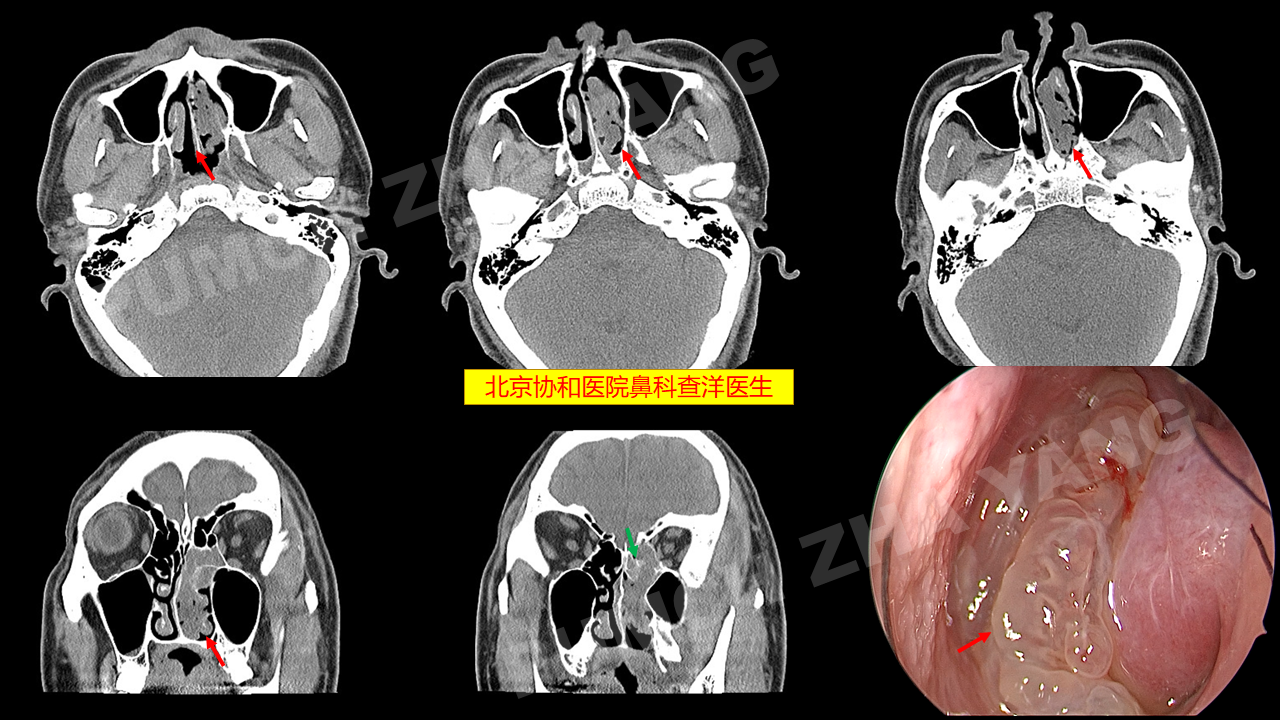

李健东大夫 的想法: 鼻腔肿瘤,戴医生在内窥镜下完美切除 - 知乎